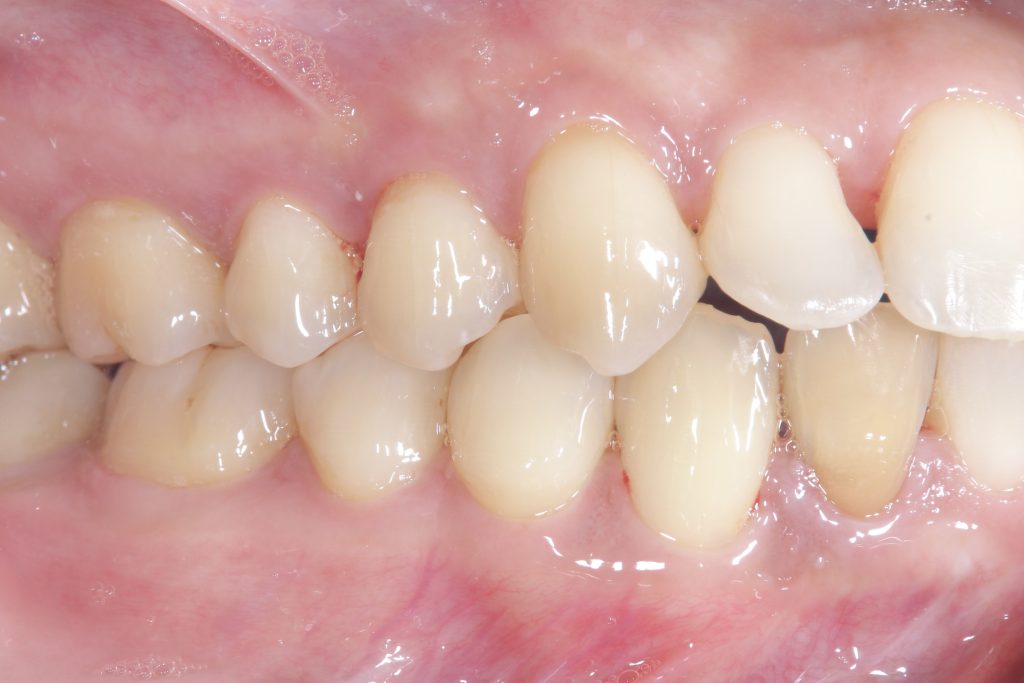

受け口の状態により、上の歯が内側に入り込み、反対の噛み合わせになっている部分が見られました。見た目の問題だけでなく、噛み合わせのバランスにも影響を与えていました。

- 前歯部交叉咬合を伴う不正咬合

- ゴムメタルワイヤー矯正

- 2024年9月6日(10ヶ月)